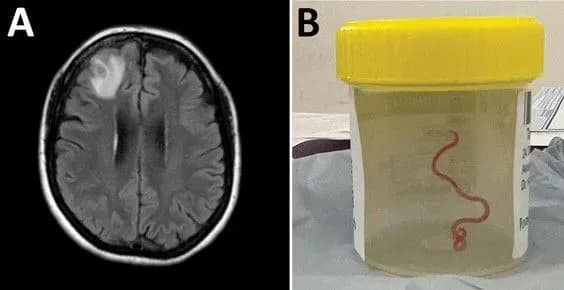

Круглого черв’яка Ophidascaris robertsi, який майже рік жив у мозку австралійки, виявили практично випадково. 64-річна жінка лягла під хірургічний ніж на біопсію. Натомість нейрохірург витягнув із її голови живого паразита. Черв’як 8 сантиметрів завдовжки та міліметр завширшки звивався у мозку. Це перший випадок, коли зміїного паразита виявили в організмі людини, не кажучи вже про мозок.

Однак, невдовзі після цього лікування вона пережила тримісячний напад забудькуватості. Магнітно-резонансна томографія головного мозку показала збільшення у правій лобовій частці. У червні 2022 року австралійка лягла на операцію, і саме тоді нейрохірург витягнув живого паразита.